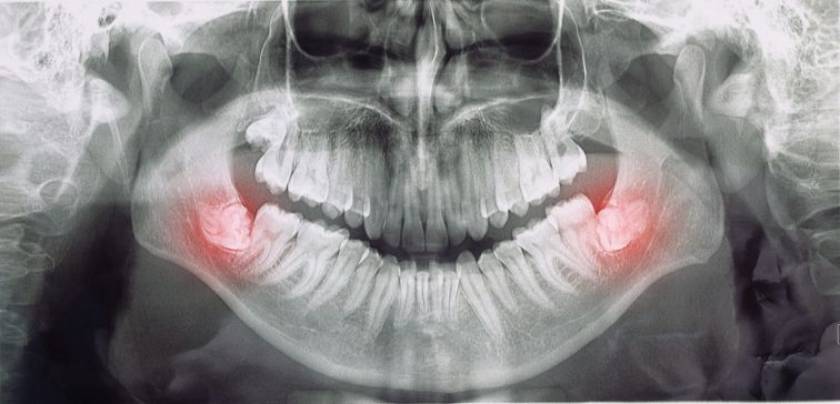

Mọc răng khôn có thể gây đau răng sưng má

Bác sĩ sẽ kiểm tra miệng của bạn để xem có thể phát hiện bất kỳ dấu hiệu nào của vấn đề hay không. Việc chụp phim X-quang là cần thiết để chẩn đoán hoặc loại trừ các vấn đề như nhiễm trùng răng hoặc áp-xe răng.